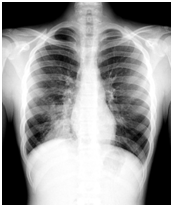

Пневмония или воспаление легких является тяжелым заболеванием органов дыхательной системы, которое может привести к серьезным последствиям и даже к летальному исходу. Пневмония — потенциально опасная для здоровья и жизни болезнь. В мировой структуре смертности она занимает четвертое место после ишемической болезни сердца, инсультов, хронической обструктивной болезни лёгких.

Пневмония может возникнуть в течение острой респираторной инфекции, гриппа так и после них. Наиболее распространенные возбудители инфекции легких: пневмококки, стафилококки, энтерококки, и микоплазмы, вирусы.

Пневмония как осложнение гриппа чаще возникает у детей до 5 лет и пожилых людей старше 65 лет, беременных женщин (в основном в последнем триместре). Также в группе риска лица со следующими патологиями: хроническими болезнями легких — ХОБЛ, бронхиальной астмой; обменными нарушениями — сахарным диабетом, ожирением; хроническими заболеваниями сердечно-сосудистой системы, почек, печени; злокачественными опухолями любой локализации; алкоголизмом.